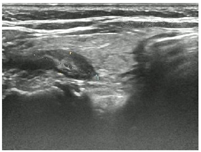

入院后行甲状腺超声示甲状腺左叶上、下极深方甲状旁腺区见2个囊实性结节,大小分别为2.9cm×1.4cm×1.1cm、2.3cm×1.4cm×1.2cm,均形态规则,边界清晰,CDFI:内见较丰富血流信号(图1,图2,图3,图4)。行甲状旁腺融合显像(显像剂:99Tcm-MIBI)示甲状腺左叶上极后上方见结节样显像剂浓聚灶,相应CT层面示椭圆形软组织密度影,边界清,大小约27.6mm×18.2mm×16.0mm。CT另见甲状腺左叶下极后下方一椭圆形软组织密度影,边界较清,大小约25mm×13.7mm×12.5mm,相应ECT层面未见显像剂摄取(图5,图6)。行嗜铬细胞瘤融合成像(显像剂:131I-MIBG)示颈部及腹部可见显像剂摄取病灶(图7,图8)。

超声图像中左侧甲状旁腺区2枚囊实性结节形态、回声、位置及血流均相似,结合实验室检查及临床病史,均提示为甲状旁腺腺瘤,但甲状旁腺融合成像仅支持甲状腺左叶上极后方结节为甲状旁腺腺瘤。甲状腺左叶下极后方结节无99Tcm-MIBI显像剂摄取,但有131I-MIBG高摄取,故综合以上考虑甲状腺左叶上极后方结节为甲状旁腺腺瘤,左叶下极后方结节为副神经节瘤。